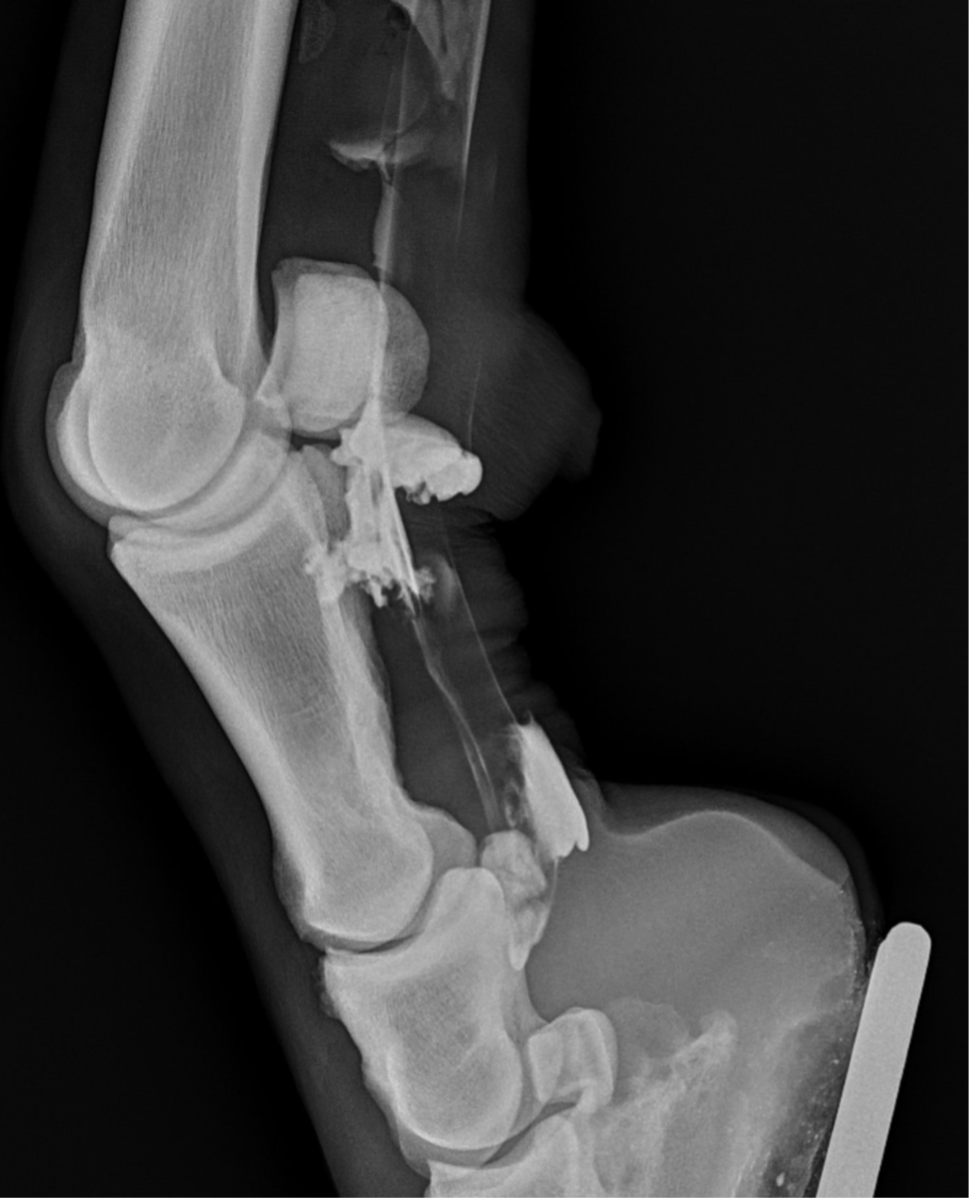

Recently, the gelding developed acute tenosynovitis of the left hind digital flexor tendon sheath (DFTS) following a competition. Despite the owner’s efforts, which included icing, wrapping, and confinement for seven days, there was no improvement in the effusion of the DFTS.

Upon further examination, contrast radiographs and ultrasound scans failed to identify any significant abnormalities apart from swollen synovium within the DFTS. To address this issue, our veterinary team administered 5mg of triamcinolone acetonide along with 20mg of HA, complemented by a compression wrap. Subsequently, the horse underwent a two-week confinement period in a small yard, followed by gradual reintroduction to exercise through 10 minutes of hand walking twice daily, with the distal limb wrapped for additional support.

However, when the condition resurfaced, our client chose to pursue tenoscopy, which fortunately revealed no clinically significant abnormalities. Following the procedure (2-weeks post-surgery), 2ml (50mg) of Arthramid was injected into the sheath, followed by two weeks of hand walking and a seamless transition back to regular riding activities.